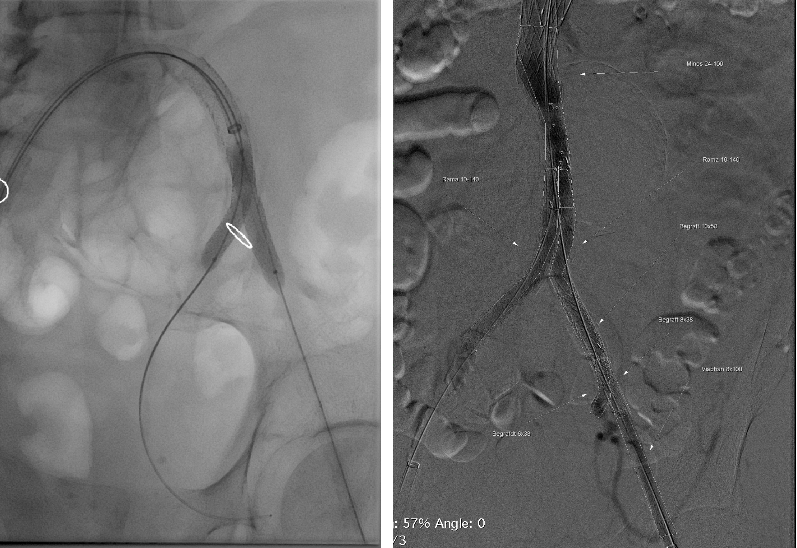

患者男性,73岁,腹主动脉瘤,高血压、血脂异常、慢性肾病。右侧股动脉中度钙化,直径5.4mm,入路面临挑战。选用Minos覆膜支架进行治疗,手术过程顺利,术后1个月的CT扫描显示无内漏且肢体通畅。该案例体现了Minos覆膜支架的Low Profile的低外径输送系统能够在狭窄和迂曲的动脉中顺利操作,为因血管条件不佳而不适合传统EVAR的患者提供了新的治疗选择。